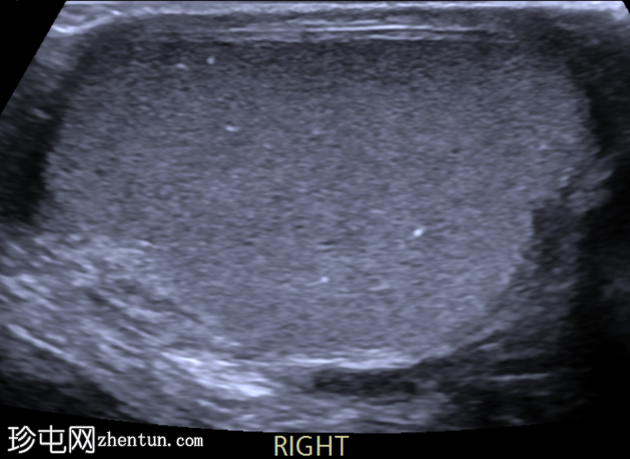

右侧睾丸正常。